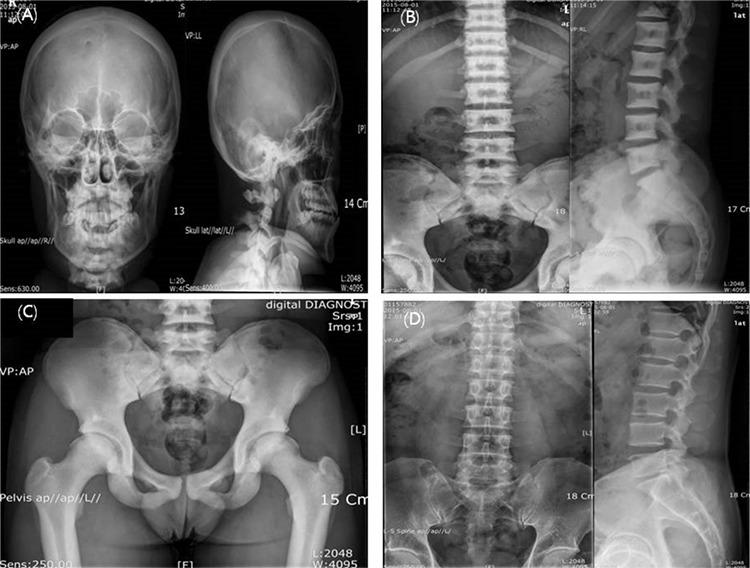

Osteopetrosis is a rare genetic disease characterized by increased bone density and bone fractures due to defective osteoclast function. Autosomal dominant osteopetrosis type 2 (ADO-2), Albers-Schonberg disease, is characterized by the sclerosis of bones, predominantly involving the spine, pelvis and the base of the skull. Here, we report a typical case of osteopetrosis in a 17.7-year-old male who carries a heterozygous c.746C>T mutation in exon 9 in the gene. The patient’s spine showed multiple sclerotic changes including sandwich vertebra. His father had the same mutation but his skeletal radiographs were normal. This is the first reported case of ADO-2, confirmed by genetic testing in a Korean patient.

骨质石化症是一种罕见的遗传性疾病,其特征是由于破骨细胞功能缺陷导致骨密度增加和骨折。常染色体显性遗传性骨质石化症2型(ADO-2),即阿尔伯斯-尚伯格病,其特征是骨骼硬化,主要累及脊柱、骨盆和颅底。在此,我们报告一例典型的骨质石化症病例,患者为一名17.7岁男性,其该基因第9外显子存在杂合性c.746C>T突变。患者脊柱显示出包括夹心椎在内的多处硬化改变。其父亲有相同的突变,但骨骼X光片正常。这是韩国首例经基因检测确诊的ADO-2病例。